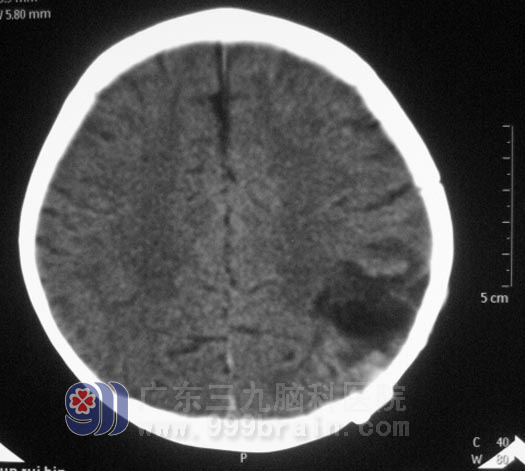

还不到两岁的冰冰,聪慧可人,正在玩耍时意外被木棍打到头上,摔倒在地,随即出现呕吐、意识障碍,急送当地医院,头颅CT检查提示:左侧顶骨凹陷性骨折,轻度大脑镰下疝,左侧顶叶挫裂伤并血肿,左侧顶部硬脑膜下出血。

入院时冰冰呈昏迷状,双侧瞳孔不等大,左侧颞顶部头皮肿胀明显。鲁明主任详细了解病情及查阅影像资料后,急诊在全麻下行左侧颞顶脑挫裂伤灶+血肿清除术+左侧颞顶颅骨碎骨取出+凹陷性骨折整复术。术中见左侧颞顶部肿胀明显,切开头皮见冒状腱膜下有积血,逐渐分离骨膜至骨折处,大量黑色不凝血性液体喷出;完全分离骨膜和帽状腱膜后见颅骨凹陷处脑组织及淤血膨出,在显微镜下彻底清除血肿及坏死脑组织。术后的她恢复很快,语言、肢体运动等功能均没有受到影响。